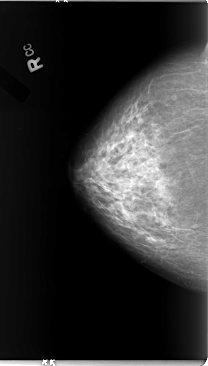

B_3080_1.LEFT_MLO

B_3080_1.LEFT_CC

LEFT_CC LINES 4760 PIXELS_PER_LINE 2816 BITS_PER_PIXEL 12 RESOLUTION 50 OVERLAY

FILE: B_3080_1.LEFT_CC.OVERLAY

TOTAL_ABNORMALITIES 1

ABNORMALITY 1

LESION_TYPE MASS SHAPE LOBULATED MARGINS ILL_DEFINED

ASSESSMENT 4

SUBTLETY 4

PATHOLOGY MALIGNANT

TOTAL_OUTLINES 1

BOUNDARY